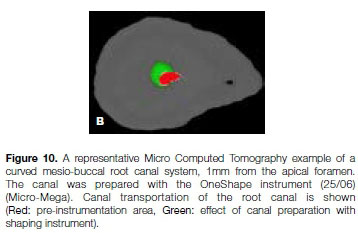

Figures 9 and 10 illustrate micro-computed tomographic images of two curved mesio-buccal root canal systems of extracted, maxillary first molar teeth at a level 1mm from the apical foramen. The example in Figure 9 shows minimal canal transportation after root canal preparation compared with that in Figure 10 which clearly shows an excessive amount of canal transportation.